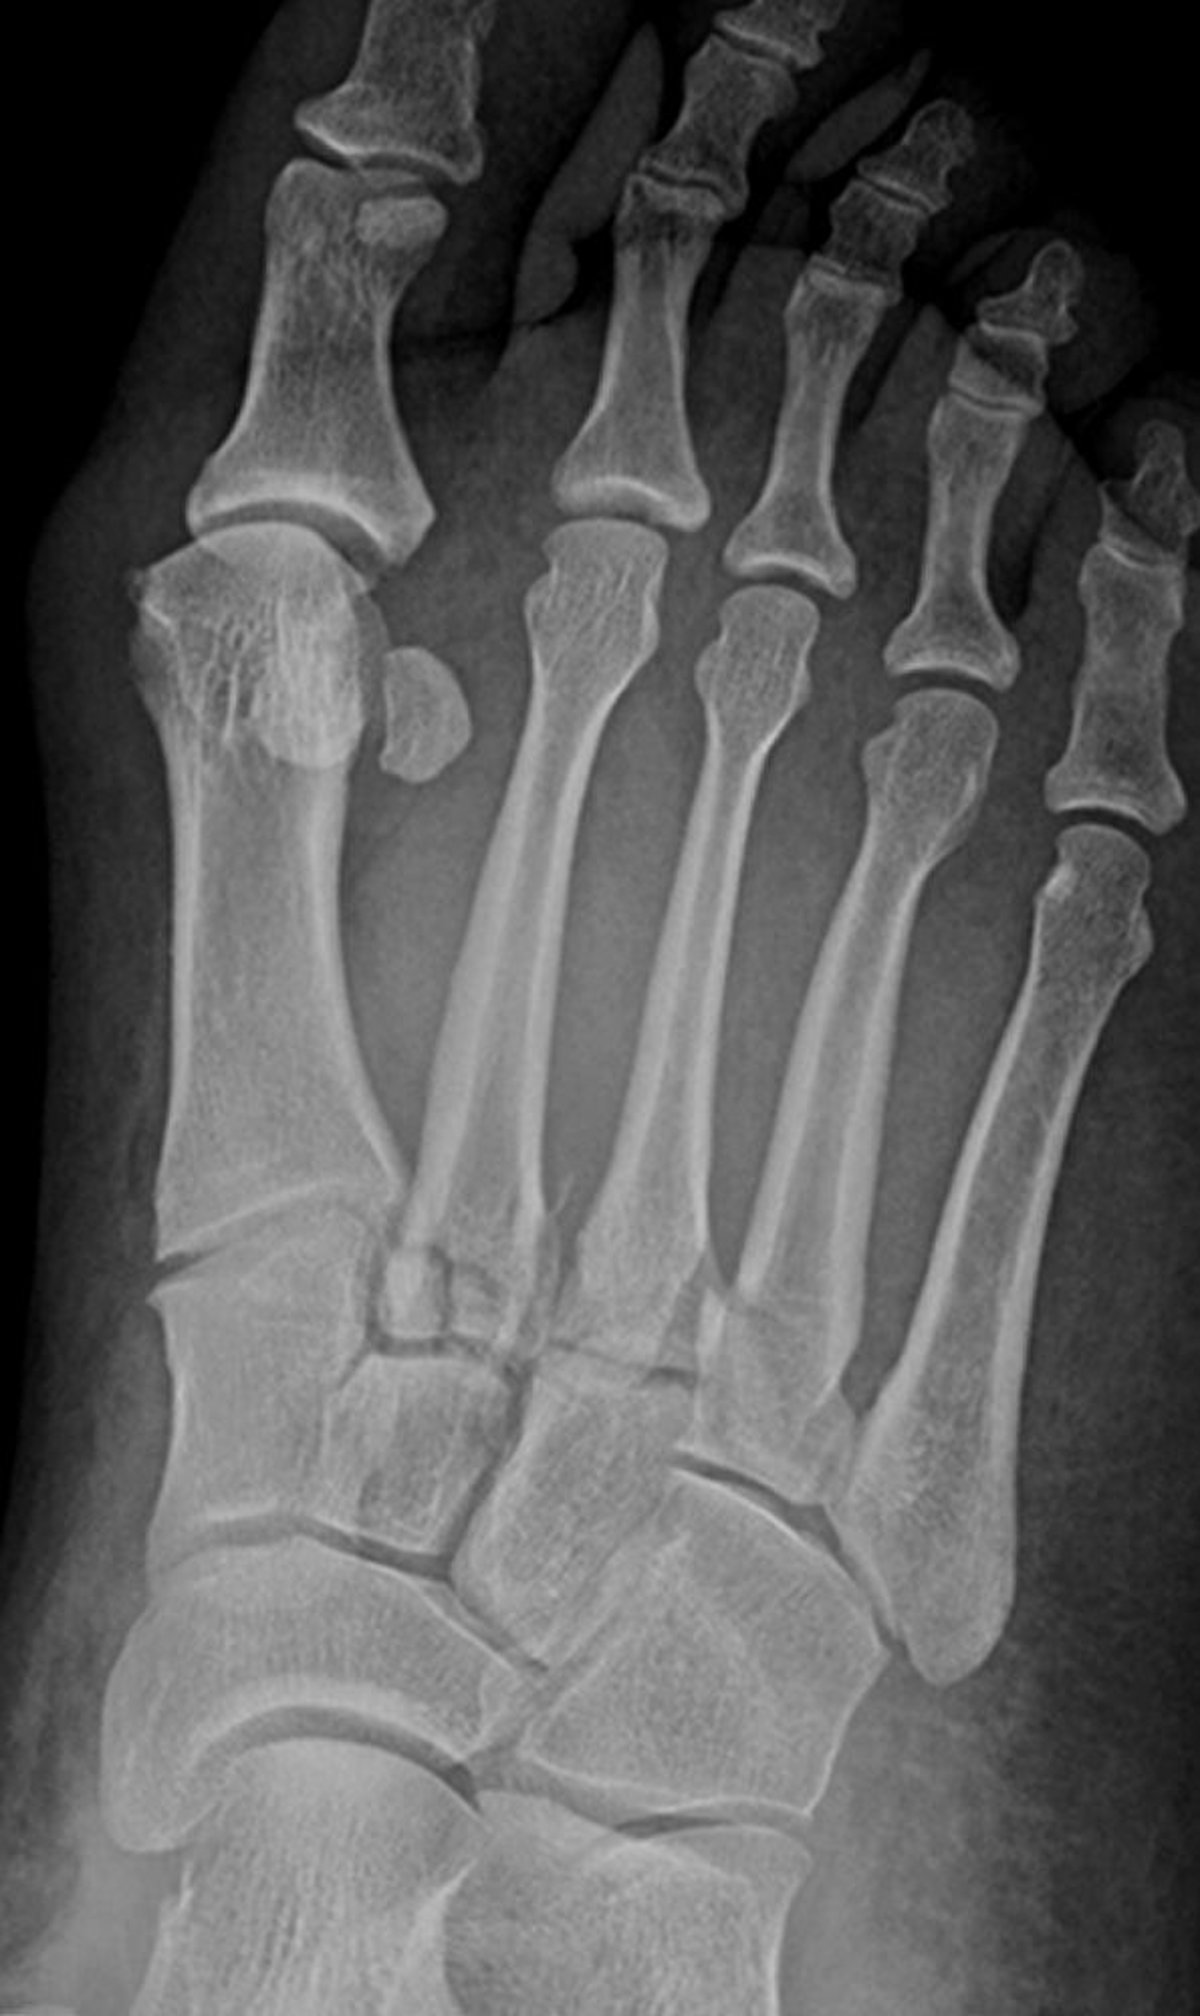

Fractures de Lisfranc

Cette radiographie montre des fractures à la base des 2e, 3e et 4e métatarsiens. Les articulations tarsométatarsiennes sont également destructurées.

Image courtoisie de Danielle Campagne, MD.